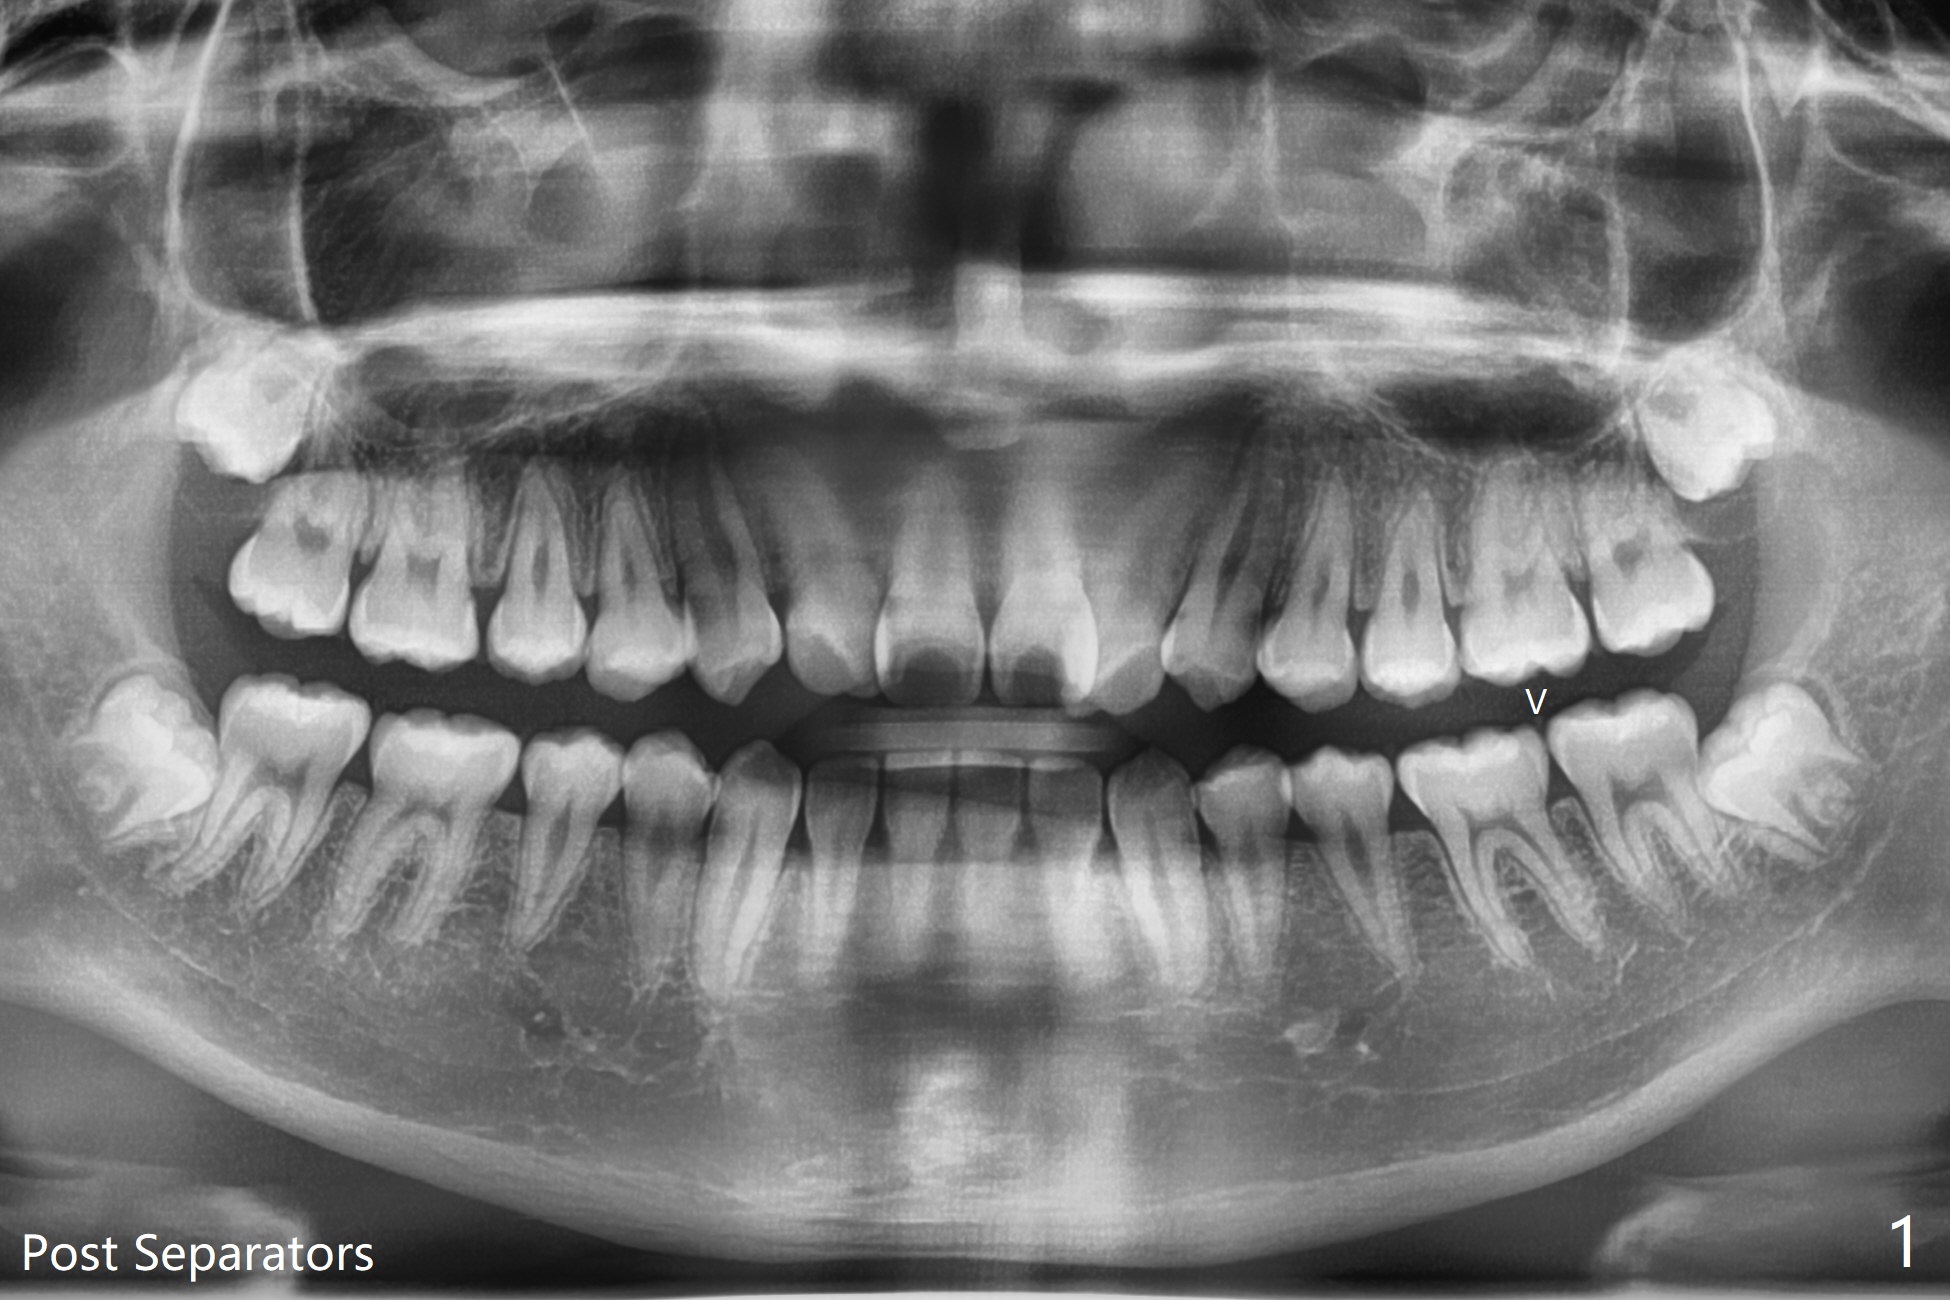

Impacted 3rd Molar Prevents 2nd Molar Band from Seating

It is difficult to place a molar band in the lower left 2nd molar of a 15-year-old man after separators (Fig.1,2). It is due to the impacted 3rd molar.